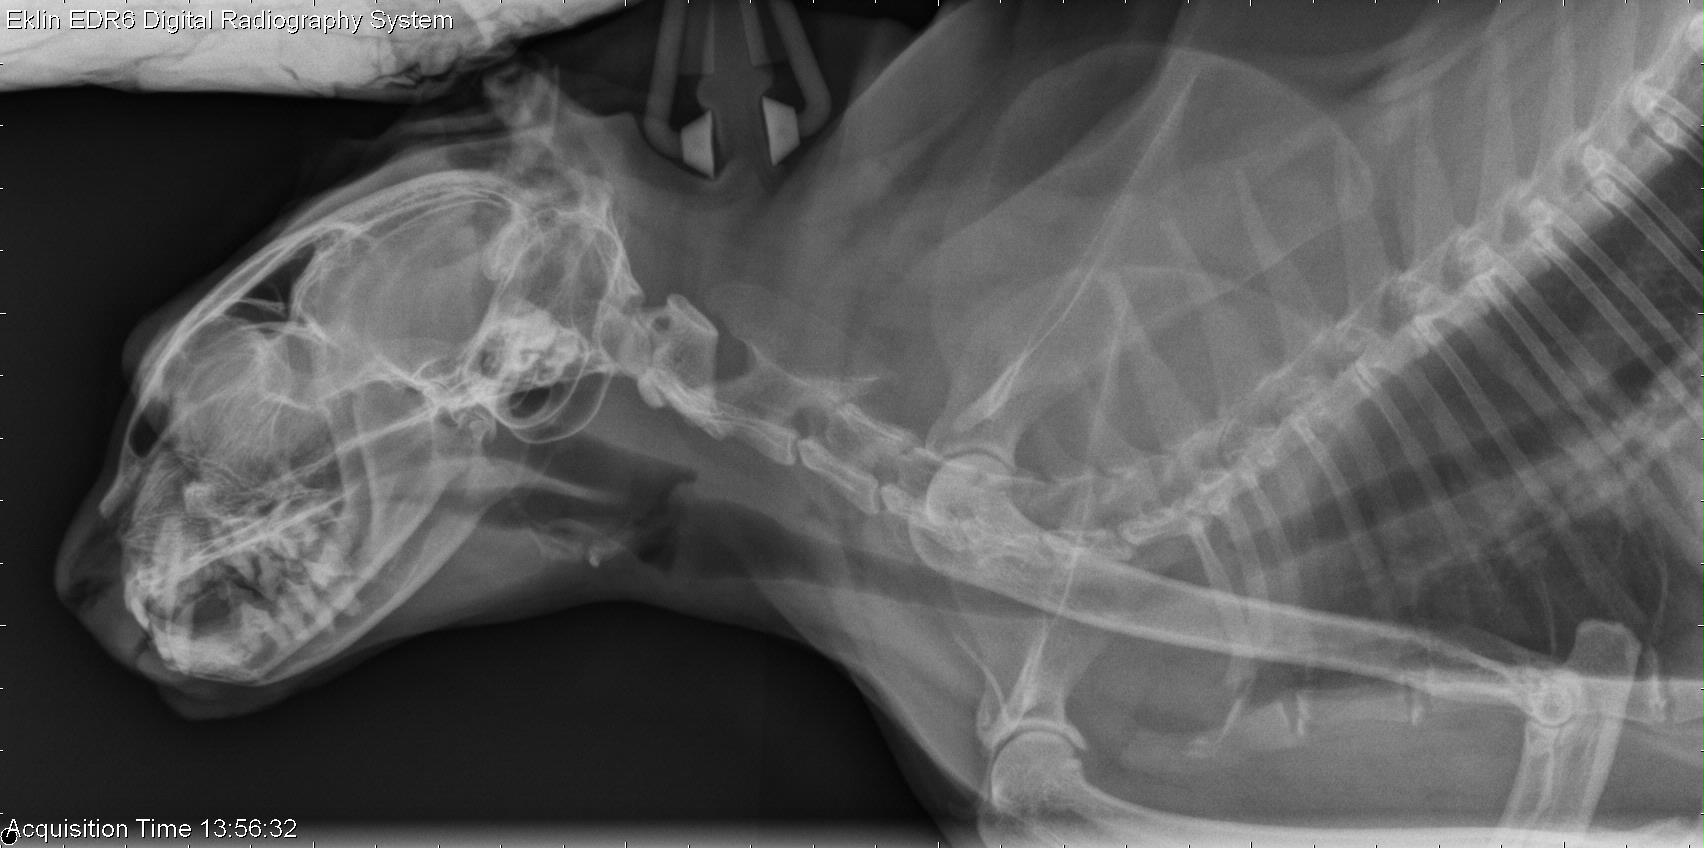

Cat X-Ray Skull . Common and important indications for radiography of the skull include nasal. in the feline, the main indications for skull radiography include trauma, nasal discharge (acute, chronic,. • during each imaging series of the skull, one of the projections. the skull is the most complex and specialized part of the skeleton; the author prefers the dorsoventral view over the ventrodorsal view, as it is easier to position the skull flat on. indications for skull radiography. It is a challenging region to evaluate with. obtain diagnostic skull radiographs for several reasons: the anatomy of the skull and nasofacial area of the dog and cat is complex, with cavities, sinuses, mandible, maxilla, dental.

Cat X-Ray Skull the author prefers the dorsoventral view over the ventrodorsal view, as it is easier to position the skull flat on. the skull is the most complex and specialized part of the skeleton; obtain diagnostic skull radiographs for several reasons: • during each imaging series of the skull, one of the projections. in the feline, the main indications for skull radiography include trauma, nasal discharge (acute, chronic,. indications for skull radiography. the anatomy of the skull and nasofacial area of the dog and cat is complex, with cavities, sinuses, mandible, maxilla, dental. the author prefers the dorsoventral view over the ventrodorsal view, as it is easier to position the skull flat on. Common and important indications for radiography of the skull include nasal. It is a challenging region to evaluate with.

Right lateral radiograph of the skull of Dog 2, taken 3 months after Cat X-Ray Skull obtain diagnostic skull radiographs for several reasons: indications for skull radiography. It is a challenging region to evaluate with. Common and important indications for radiography of the skull include nasal. the skull is the most complex and specialized part of the skeleton; in the feline, the main indications for skull radiography include trauma, nasal discharge (acute,. Cat X-Ray Skull.

13 year old DSH cat Cat X-Ray Skull • during each imaging series of the skull, one of the projections. indications for skull radiography. in the feline, the main indications for skull radiography include trauma, nasal discharge (acute, chronic,. the skull is the most complex and specialized part of the skeleton; the author prefers the dorsoventral view over the ventrodorsal view, as it is. Cat X-Ray Skull.